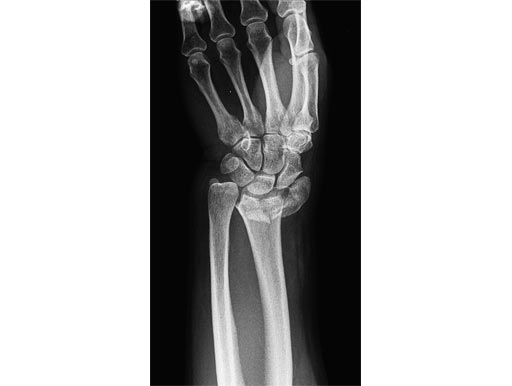

54-year-old female with 23-C3 fracture after fall

External fixator due to severe soft-tissue trauma. Palmar plate 1 week later. .